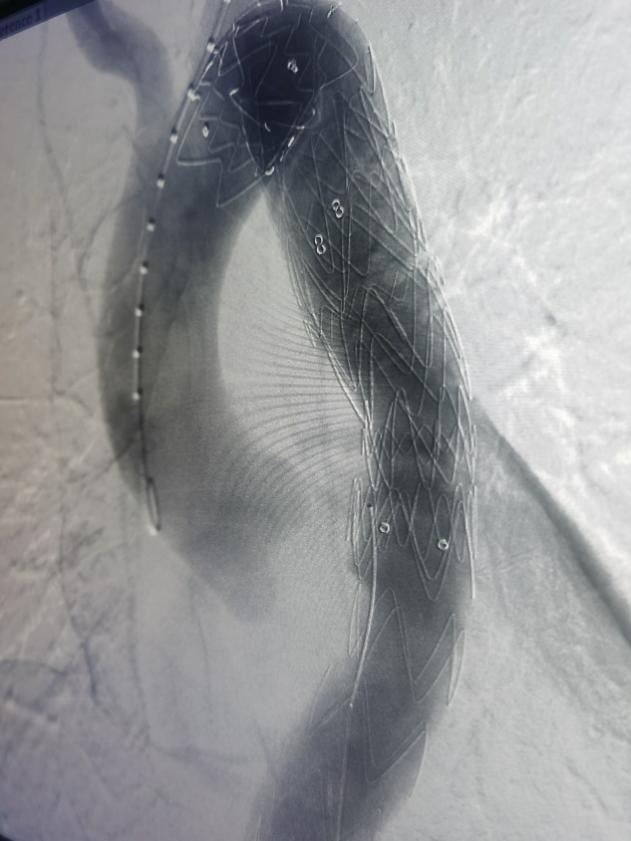

经过胸心外科、介入科、麻醉手术室、超声科多学科协作,于11月4日下午4点在急诊局麻下行胸主动脉覆膜支架夹腔内隔绝术,术中精准释放覆膜支架,复查血管造影显示,封闭主动脉破裂口,无内漏,支架位置良好,术区相关动脉血管显影良好,“不定时炸弹”成功拆除。术后给予患者抗板、止痛、控制血压等相应治疗,患者目前恢复良好,已顺利出院。该手术的成功,充分体现了我院多学科积极协作的团队精神。